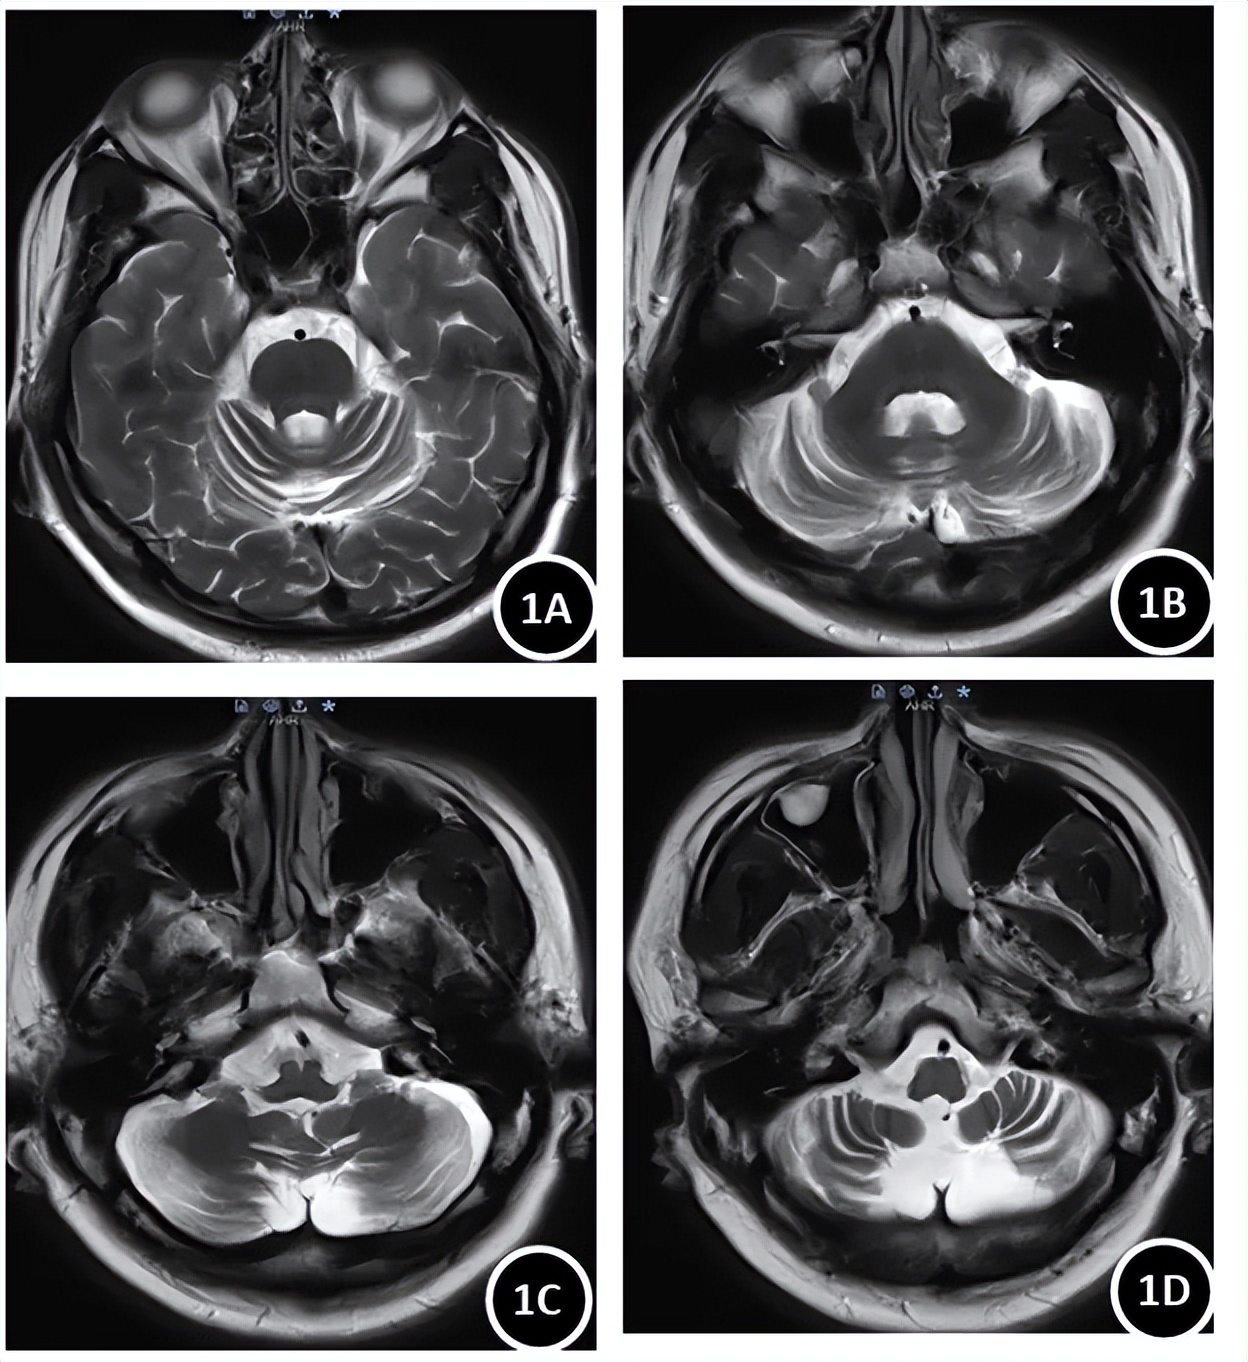

4.影像学检查

头颅MRI平扫(图1)示小脑萎缩(双侧小脑脑沟、裂增宽)。头颅MRI灌注成像示小脑萎缩伴稍低灌注。因患者家属要求积极完善检查,排除非遗传性病因,在征得患者同意后完善腰椎穿刺脑脊液检查:有核细胞数正常,潘氏试验阳性,脑脊液蛋白0.9 g/L↑,脑脊液免疫球蛋白G 57.1 mg/L↑,脑脊液白蛋白464 mg/L↑;血清和脑脊液均未见寡克隆区带;脑脊液病理未见明显异常;脑脊液和血清小脑抗体谱19项(-),血TBA(-),扩大抗体谱中血抗Drebrin抗体IgG(+)。查阅文献,抗Drebrin抗体IgG阳性的患者多出现癫痫发作、记忆力损害,表现为边缘叶脑炎或大脑炎,与该患者临床表现不符,故不考虑其有意义。

图1 患者头颅磁共振扫描T2序列

注:A~D为小脑横截面自上而下显示。